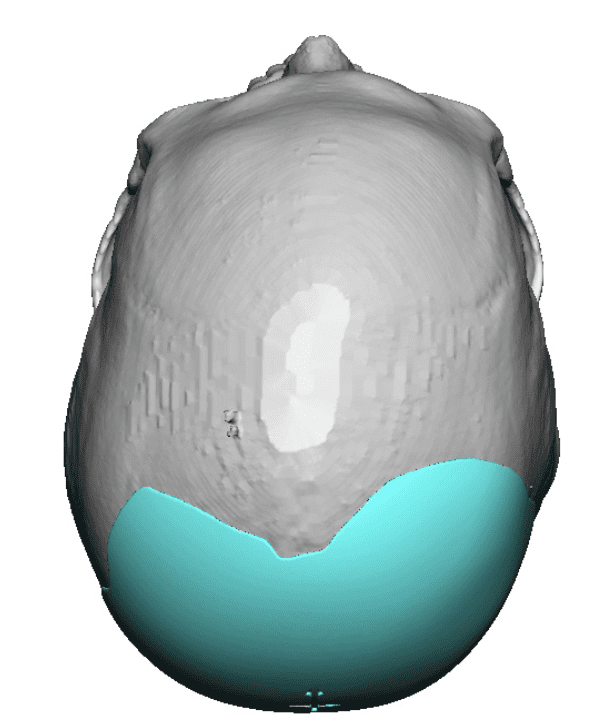

Desire for a higher and more prominent crown of the skull.

Crown of skull augmentation using a custom skull implant.

Desire for a higher and more prominent crown of the skull.

Crown of skull augmentation using a custom skull implant.